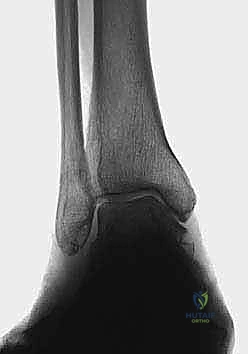

2. التصوير بالأشعة السينية بوضعية الوقوف (Weight-bearing X-rays)

هذا هو حجر الأساس في التشخيص. الأشعة العادية والمريض مستلقٍ لا تظهر الحجم الحقيقي للتشوه. يطلب الدكتور هطيف صوراً خاصة والمريض يحمل وزنه كاملاً على قدميه.

* المنظر الأمامي الخلفي (AP View): لتقييم المسافة المفصلية وتحديد زاوية سطح الساق (Tibial Anterior Surface Angle - TAS).

* منظر سالتزمان (Saltzman View): وهو منظر إشعاعي متخصص جداً لتقييم محاذاة الكعب الخلفي بالنسبة لمحور الساق، وهو أمر حاسم في التخطيط الجراحي.